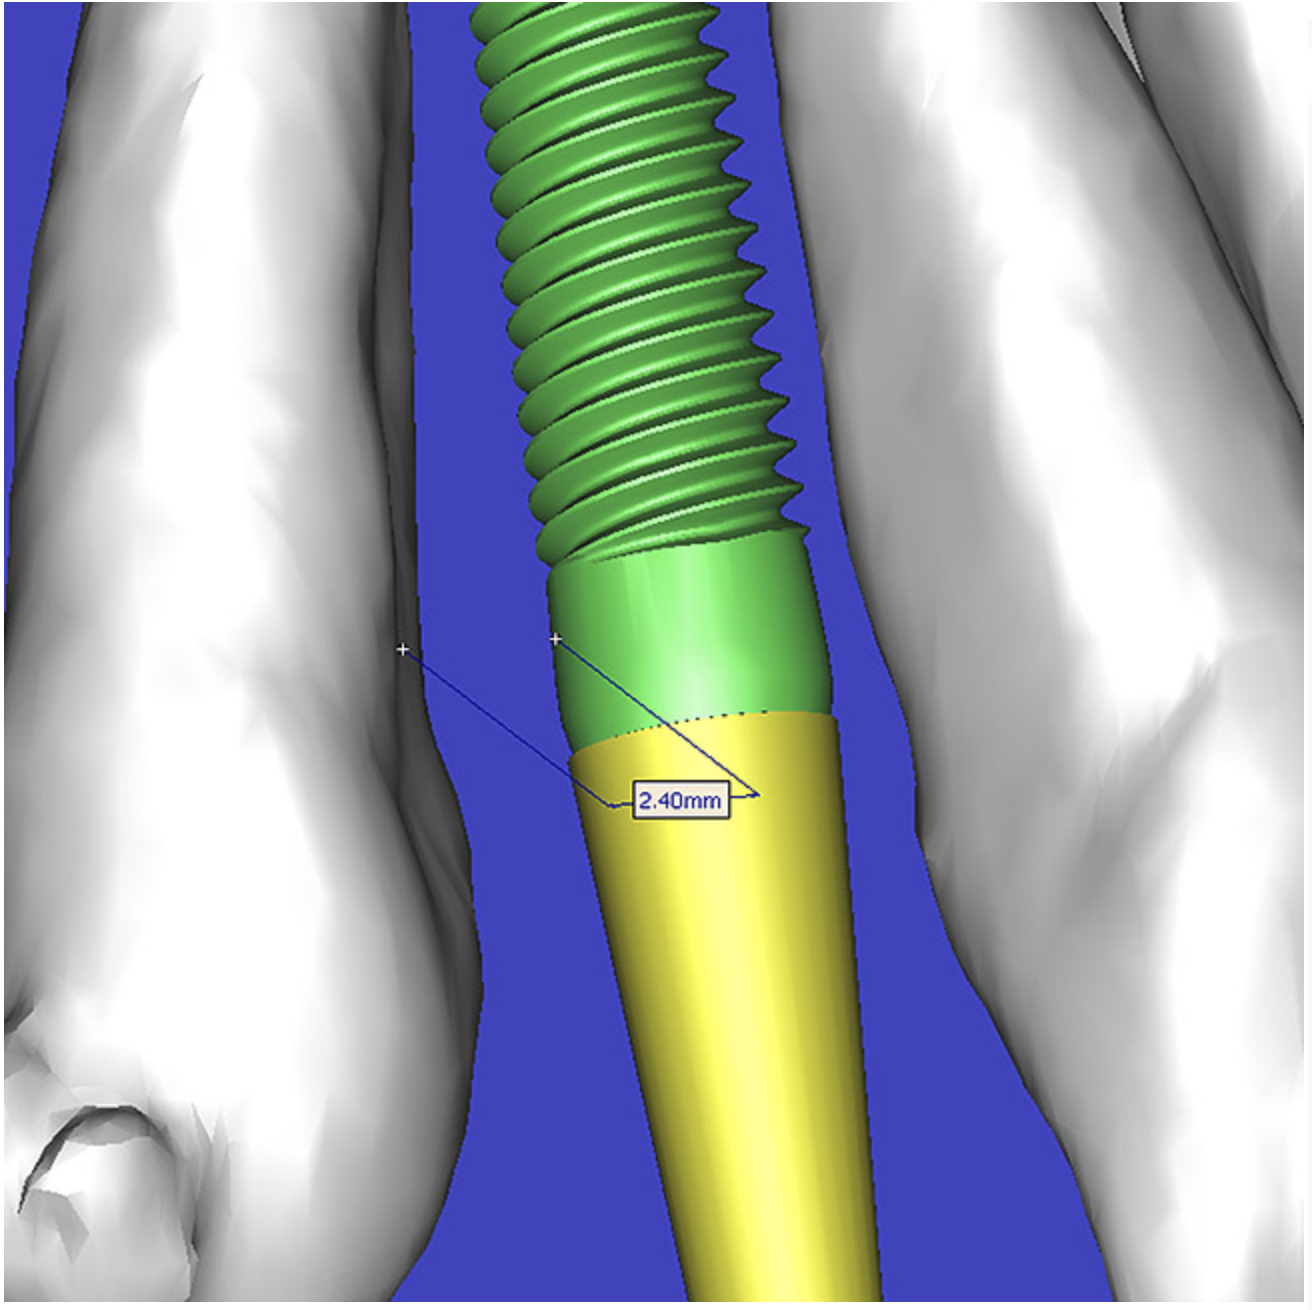

This case contained bilateral concavities, which led to three treatment options being considered: (1) place the bilateral implants and do nothing about the concavity and lack of root eminence; (2) place a soft-tissue graft to plump out the tissue to simulate a root eminence; or (3) add bone to fill out the defect. Additional suboptions also came into play, such as the type of bone graft procedure (allograft or autogenous, particular cancellous or cortical particles, block graft). The left lateral site revealed a thinner facial-lingual crestal dimension (Figure 5A). The simulated implant was placed within the TOB, and a simulated bone graft (available as an upgrade tool for SIM/Plant) was added to the facial, helping determine the proper course of treatment (Figure 5B).

Figure 5a  The software (A) revealed a thinner facial-lingual crestal dimension, and (B) allowed a simulated bone graft to be placed.

Figure 5a

Figure 5b  The software (A) revealed a thinner facial-lingual crestal dimension, and (B) allowed a simulated bone graft to be placed.

Figure 5b